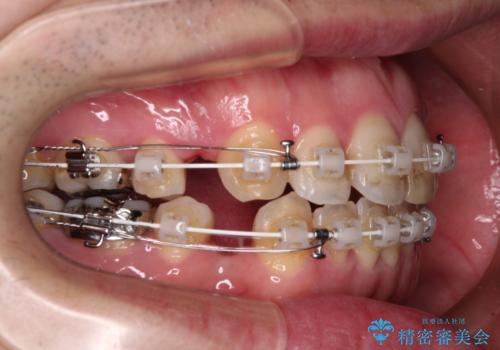

- 矯正装置

- 審美装置

口元の突出感を改善するために上下左右の第一小臼歯4本を抜歯し、ワイヤー装置にて矯正治療を行うこととしました。